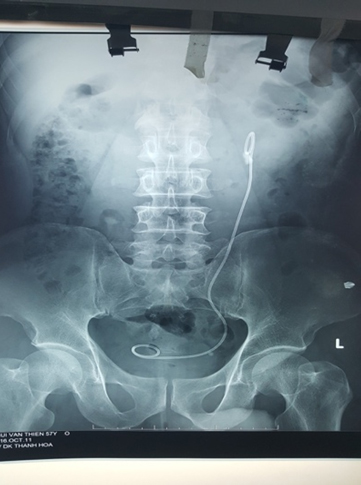

Hình ảnh X-quang đặt sonde JJ trước mổ 2 tuần.